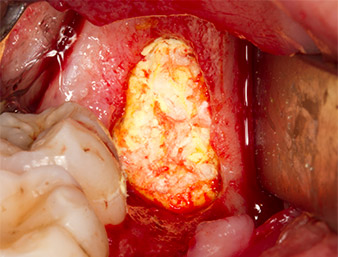

The tissue above the root remnant was not completely ossified and consisted for the most part of granulation tissue modified by inflammation (Fig. 4).

Granulation tissue

Fig. 4: Two Langenbeck retractors and a raspatorium expose the operating area. Granulation tissue of the incompletely healed first osteotomy can be seen.